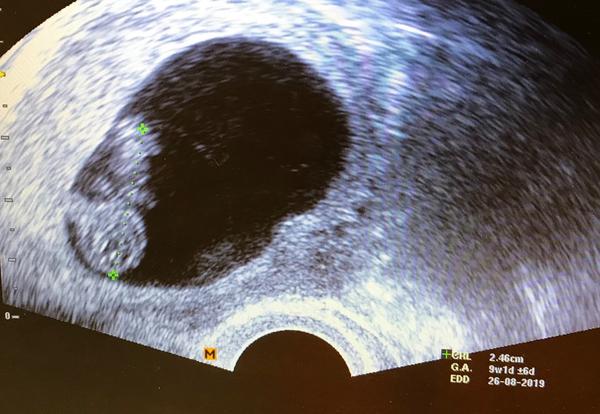

Tak méďa je na místě, mrská se, srdce mu tluče jako o závod a podle utz vypadá o tři dny starší, ne 7+2 ale 7+5, i když je to zatím fakt jen orientační. Asi se má u mě dobře 😁